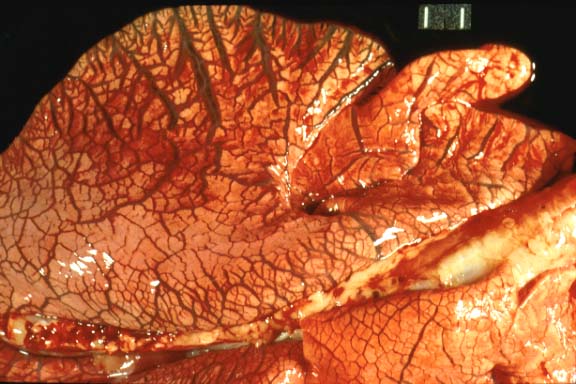

- Gross Pathology: Necropsy findings included blood-stained

perineum, hemorrhage throughout the lumen of the small and large

intestines, and pulmonary edema. Color photo transparencies of

the lungs and intestinal tract are included.

- Case 16-2. Lung. Interlobular septa are markedly expanded

by edema fluid.

- Case 16-2. Spiral colon and jejunum. Colon & small

intestine is segmentally filled with dark red hemorrhage-stained

ingesta. The mesentar appears diffusely edematous.